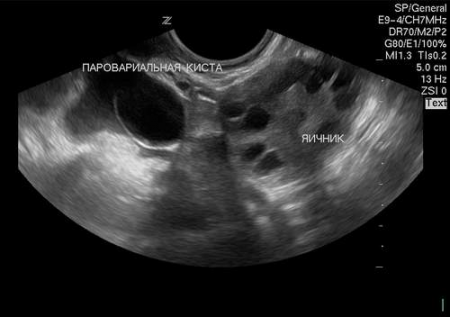

При больших размерах кисты врач может заподозрить ее наличие уже при осмотре и прощупывании живота. Из инструментальных методов в диагностике помогает УЗИ брюшной полости, на котором можно увидеть полостное образование. Для верификации диагноза проводится диагностическая лапароскопия параовариальной кисты яичника. Суть этого метода заключается во введении в брюшную полость лапароскопа (телескопическая трубка) с помощью которого можно увидеть кисту, ее размеры, точное местоположение, взять биопсию для дифференцирования с опухолями яичника.

Параовариальная киста яичника: фото УЗИ